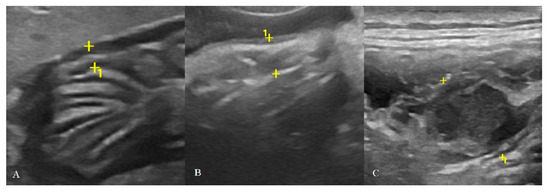

Between 2017 and 2020, a total of 31 cats underwent B-mode US and CEUS examination. Two cats were excluded because of the poor clip’s quality obtained from the CEUS examination and quantitative analysis could not be performed. All the gastric neoplasms were confirmed by cytological, histological and/or immunohistochemical diagnosis as lymphoma divided in LGAL and HGAL. No adverse effects were noted in any of the patients. A total of 29 cats were included in the study: six healthy (HEA) cats in the control group (mean age 2.08 ± 0.5 years), nine in the inflammatory (INF) group (mean age 6.4 ± 3.3 years), three in the LGAL group (mean age 12 ± 1 years) (Figure 2), and 10 in the HGAL group (mean age 9.4 ± 3.7 years) (Figure 3). All the HEA cats included in the control group were followed up on and checked 12 months after the first examination, confirming the absence of clinical and ultrasonographic signs of gastric disease.

Figure 2. Cat affected by gastric low-grade lymphoma (LGAL) showing: (A) diffuse reduced layer definition associated with mild increases in wall thickness (3.8 mm between the asterisks) on B-mode examination; (B,C) B-mode (B) and contrast-enhanced ultrasonography (CEUS) (C) clip acquired using dual-mode visualization in order to better identify the gastric wall during CEUS examination.